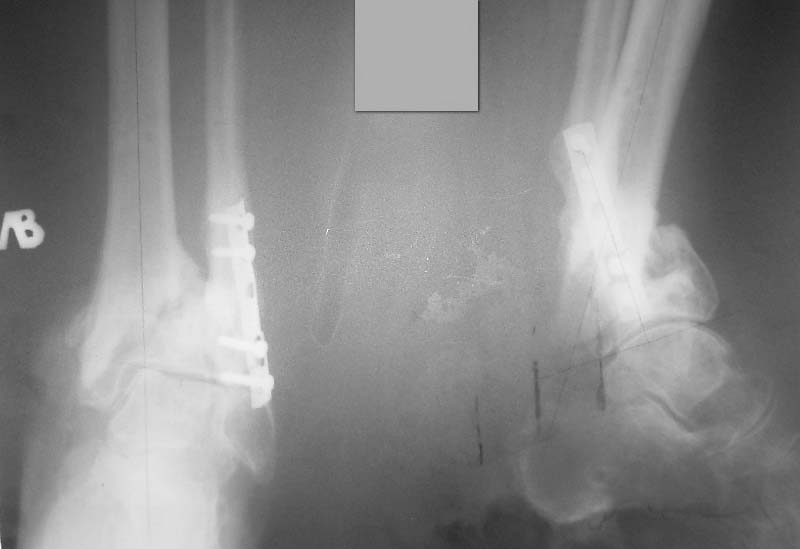

Уважаемые коллеги! Интересно ваше мнение по тактике лечения данной пациентки.Женщина 72 л соматически сохранная, умеренно полная, в мае прошлого года получила бытовую травму - открытый оскольчатый внутрисуставной перелом дистального метаэпифиза большеберцовой кости (Gustilo III-A) и поперечный перелом н/з малоберцовой кости со смещением отломков. Оперирована ургентно - открытая репозиция отломков малоберцовой кости, остеосинтез пластиной. ПХО раны голеностопного сустава, стабилизация отломков большеберцовой кости стержневым аппаратом. Репозиция отломков удовлетворительная (варус до 5 гр, рекурвация до 5 гр) - сильно за ней не гонялись, много осколков. В дальнейшем заживление ран первичное. Аппарат до 3 мес, затем гипсовая лонгета. Общий срок иммобилизации и разгрузки нижней конечности 4,5 мес - разрешена нагрузка после клинических и рентгенологических? признаков сращения. Последние 4 мес из поля зрения выпала, появилась сегодня. Беспокоят сильные боли при ходьбе, деформация голени, хромота. Р-контроль прилагается - варус 16 гр, рекурвация 35 гр (прошу прощения за качество снимков). Клинически варусно-рекурвационная деформация н/з голени, подвижность в н/з, боль. Движения в голеностопном суставе разгибание-сгибание 0/0/20. Трофика не нарушена, рубец области медиальной лодыжки плотный, спаян с подлежащими тканями. Больная хочет ходить без боли на ровной ноге (что вполне естественно). Возникает вопрос - как этого добиться? Удаление металлоконструкций, остеотомия малоберцовой на мой взгляд не обсуждаются - выполняются при любом из выбранных методов лечения (далее как мне видится в порядке предпочтения): - коррекция деформации аппаратом Илизарова с последующим БИОС ретроградным стержнем типа T2 AAN или аналогами (читал за и против данного метода, но по моему он единственный обеспечит больной раннюю нагрузку и стабильность пусть даже ценой потери ГСС (который и так уже потерян ИМХО) и ПТС). -коррекция деформации аппаратом Илизарова с оставлением этой фиксации как окончательной (необходимо ли выполнение свободной костной пластики). -открытая репозиция, остеосинтез LCP с костной пластикой. Данный метод на мой взгляд не позволит добиться хорошей стабильности, учитывая небольшой дистальный отломок и пороз кости (уже при первой операции обращала на себя "пустота" метаэпифиза), будет сопряжен с дополнительной иммобилизацией, как следствием потерей функции голеностопного сустава, невозможностью ранней нагрузки конечности. Кроме того, наиболее травматичное вмешательство, а м/ткани этой области скомпрометированы первичной травмой - как пойдет заживление. Таково мое видение проблемы. Женщине очень хочется помочь, поэтому буду рад выслушать все мнения, доводы "за" и "против" какого-то метода, другую тактику.

Уважаемый Антон! Видимо, Ваша пациентка повторно травмировала ногу, т.к. произошел повторный перелом малоберцовой кости и угловая деформация на уровне верхнего винта. К тому времени костная мозоль была еще слаба, и метаэпифиз б/берцовой кости "съехал" кпереди. Что делать? Сначала диагноз: неправильно сросшийся перелом метаэпифиза большеберцовой и н/3 малоберцовой костей, рекурвационная деформация. Из диагноза вытекает тактика: корригирующая остеотомия обеих костей, повторный остеосинтез. Остеотомию большеберцовой кости следует проводить на уровне верхнего края дистального отломка по профильному снимку, поперечно, малоберцовой кости - на уровне верхнего винта. После остеотомии следует совместить оси проксимального отломка и таранной кости, устранить угловую деформацию (она разная у обеих костей). Если останутся щелевидные дефекты (спереди), заполнить их аутокостью. Остеосинтез лучше проводить пластиной с угловой стабильностью "лист клевера", малоберцовой - 1/3 трубчатой (можно ту же пластину поднять на 2 отверстия) При расположении пластины по передней поверхности б/берцовой кости не забыть спилить и сровнять нижнюю часть пластины. Можно располагать и снутри, в этом случае после остеотомии и репозиции будет необходима краевая резекция дистального фрагмента, т.к. он будет выступать в виде ступени кнутри, эту же кость можно использовать для пластики. Возможна фиксация в Аппарате Илизарова - менее предпочтительный вариант. По доступам не могу советовать, но если возможно - передний дугообразный классический для большеберцовой и наружный для м/берцовой. Открывать кожу шире, для этого продлить доступ дистальнее внутренней лодыжки.

Частота ложных суставов и повторных смещений костных отломков после оперативной стабилизации переломов пилона доходит до 30%. Каждый, кто занимается лечением таких повреждений, наверняка сталкивался с такими осложнениями. Однако лечить такие осложнения в моральном, да и в оперативном плане проще, чем свежие переломы пилона (особенно Ruedi III), поскольку к этому времени становится более или менее понятной судьба голеностопного сустава. Если в достаточной мере владеете блокированным остеосинтезом, то самым оптимальным вариантом, с моей точки зрения, будет следующий. С переднемедиального и латерального доступов выполнить поперечную остеотомию большеберцовой и малоберцовой костей в плоскости параллельной плоскости голеностопного сустава на расстоянии около 3 см от самого сустава. Это минимальное расстояние, которое позволит расположить три блокирующих винта стержня. Важен выбор самого стержня. В данном случае больше всего подходит стержень ChM, имеющий на дистальном конце помимо отверстий в сагиттальной и фронтальной плоскостях и отверстия под углом в 45 градусов, причём на минимальном расстоянии друг от друга. Остетомию и последующую репозицию костных отломков мы выполняем в репозиционном спицевом аппарате. Стержень антеградный. В данном случае не вижу никаких оснований в применении ретроградного стержня, проходящего через здоровый подтаранный и через голеностопный сустав с его до конца неопределённой функцией. Образовавшийся дефект по переднемедиальной поверхности должен быть заполнен костным трансплантатом. Пример похожего случая из нашей практики - в приложенном файле.